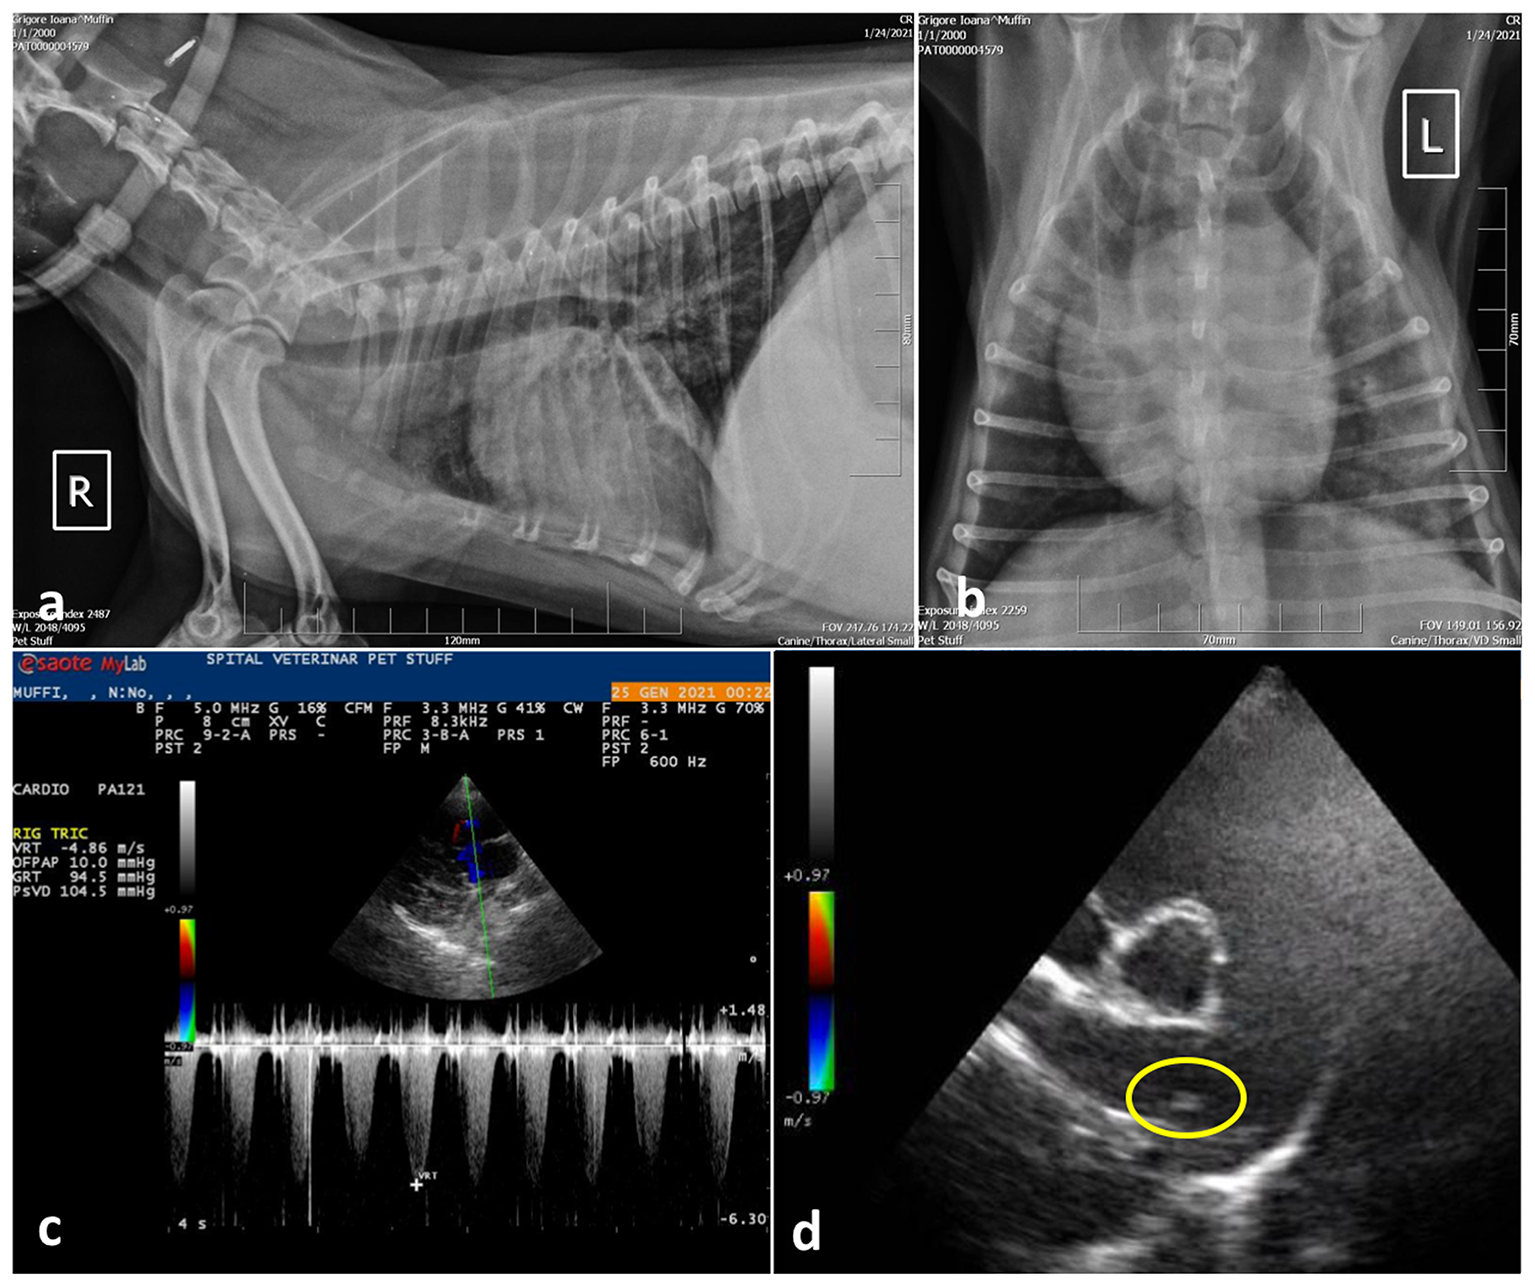

Following initial stabilization, a radiographic examination of the thorax and cardiac point of care ultrasound (POCUS) were performed. Radiology revealed small areas of interstitial pulmonary pattern and pronounced peribronchial infiltration around the large bronchi (Figures 1a, b). Parasitic pneumonia was suspected and a broncho-alveolar lavage was recommended but declined by the owner.

Figure 1

Case 1, thoracic radiographs: (a) Note the small distribution of areas with diffuse interstitial pulmonary pattern and pronounced peribronchial infiltration around the large bronchi; (b) Ventro-dorsal projection of the thorax radiography showing marked cardiomegaly with right ventricular enlargement; (c) Spectral Doppler study using continues wave revealed tricuspid regurgitant (TR) flow with a peak velocity >4.8 m/s suggesting severe PH (PG > 90 mmHg) and; (d) Right parasternal short axis view, slightly oblique for pulmonary trunk and right pulmonary artery optimal visualization. The main pulmonary artery is distended and parallel echogenic lines separated by a hypoechoic region were observed in the right main pulmonary artery (encircled area), suggesting a tubular structure, most probably the worm profile.

The cardiac POCUS images were reviewed by the cardiologist and showed signs of severe pulmonary hypertension (PH) with right ventricular enlargement, systolic flattening of the interventricular septum, the pulmonary artery to aorta ratio >1.0 and a peak tricuspid regurgitation velocity of ~4.86 m/s, PG 94 mmHg. In addition, parallel echogenic lines separated by a hypoechoic region were observed in the right main pulmonary artery in transverse and longitudinal views (right parasternal long axis 5 chambers and right parasternal short axis heart base) (Figures 1c, d). Type 5 PH was diagnosed, and further heartworm (Dirofilaria immitis) testing was performed by collecting a sample of peripheral blood, which was tested directly by means of semiquantitative PCR, and serologically by means of a rapid test (Idexx SNAP 4Dx Plus), respectively. Both exams came negative.